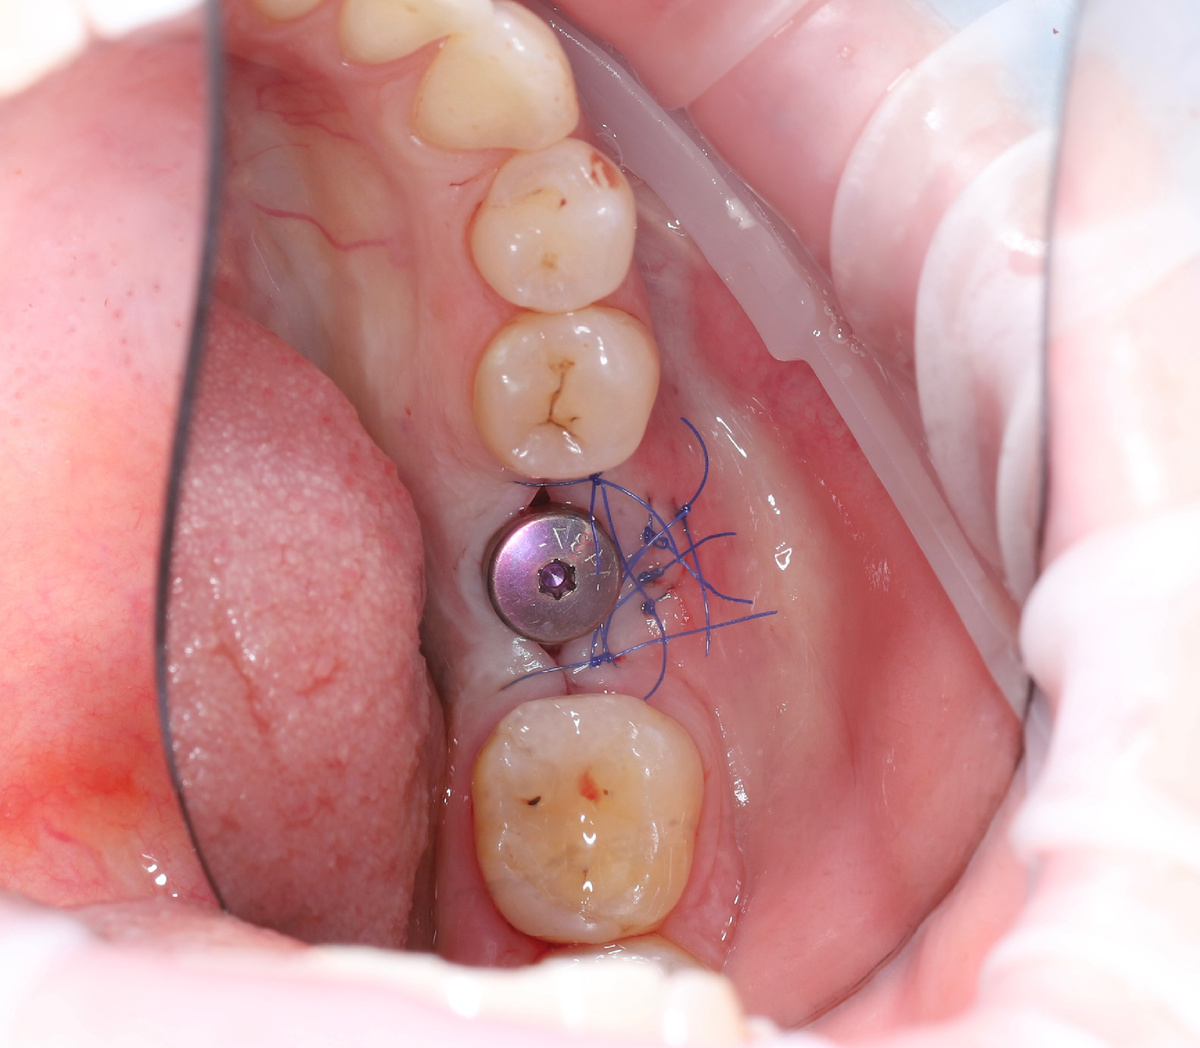

Наложение швов (ушивание лунки или раны) — это стандартная современная практика при различных операциях в полости рта, которая сильно упрощает жизнь пациенту. Основные цели - защита, комфорт и ускоренное заживление. 1. Сближение краев раны. После удаления, особенно зуба мудрости или многокорневого зуба, края десны остаются «раздвинутыми». Швы физически стягивают их, значительно уменьшая размер открытой раны. Меньше рана - меньше риск попадания пищи и бактерий, быстрее заживление. 2. Удержание кровяного сгустка. Это главная функция! Кровяной сгусток - основа заживления. Швы создают над лункой «защитный купол» из десны, который надежно фиксирует сгусток, не давая ему выпасть. Это лучшая профилактика альвеолита («сухой лунки») - самого частого и болезненного осложнения. 3. Остановка кровотечения. Швы мягко сдавливают сосуды в краях десны, помогая надежно остановить капиллярное кровотечение. 4. Защита от инфекции. Сомкнутая рана — барьер для бактерий из полости рта и частичек пищи. 5.

1. Сближение краев раны. После удаления, особенно зуба мудрости или многокорневого зуба, края десны остаются «раздвинутыми». Швы физически стягивают их, значительно уменьшая размер открытой раны. Меньше рана - меньше риск попадания пищи и бактерий, быстрее заживление.

2. Удержание кровяного сгустка. Это главная функция! Кровяной сгусток - основа заживления. Швы создают над лункой «защитный купол» из десны, который надежно фиксирует сгусток, не давая ему выпасть. Это лучшая профилактика альвеолита («сухой лунки») - самого частого и болезненного осложнения.

3. Остановка кровотечения. Швы мягко сдавливают сосуды в краях десны, помогая надежно остановить капиллярное кровотечение.

4. Защита от инфекции. Сомкнутая рана — барьер для бактерий из полости рта и частичек пищи.

5. Снижение риска кровотечения при случайной травме или неаккуратном движении в первые часы.